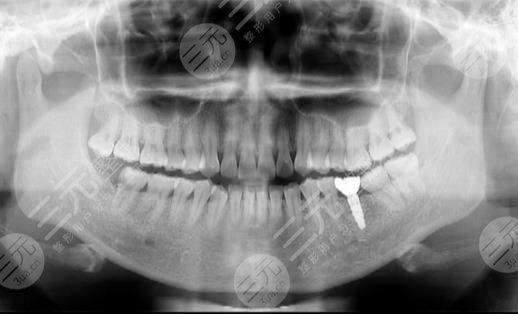

种植牙主要分为两大部分,第1个则是牙根的植入,牙根采用的是和人体骨骼能相容的钛合金,所以植入以后不会产生任何的排斥反应,而牙冠则采用和牙齿坚硬程度差不多的合规材料来做。整个过程并不是一蹴而就的,前前后后我也去医院多次,每次去都能感觉到这里医生护士的用心,这消除了我看牙的恐惧。

种植牙虽然前后要进行多次操作,不过每次操作时间并不长,在植入牙冠之时仅用了半个小时就好了,而植入牙冠是在麻醉的状态下进行的,所以看牙的时候也没有明X的痛感,对此我较为的满意。两个月以后,整个步骤都全部完成,而我也补上了此前缺失的牙齿,牙齿补上以后,我整个人都自信了许多,讲话不再漏风,咀嚼吃东西也更加的利索,对此我较为的满意。在这里要劝大家,如果牙齿有问题的话,一定要第一时间到专业机构去做诊疗,不要一拖再拖,这样会造成严重的后果。